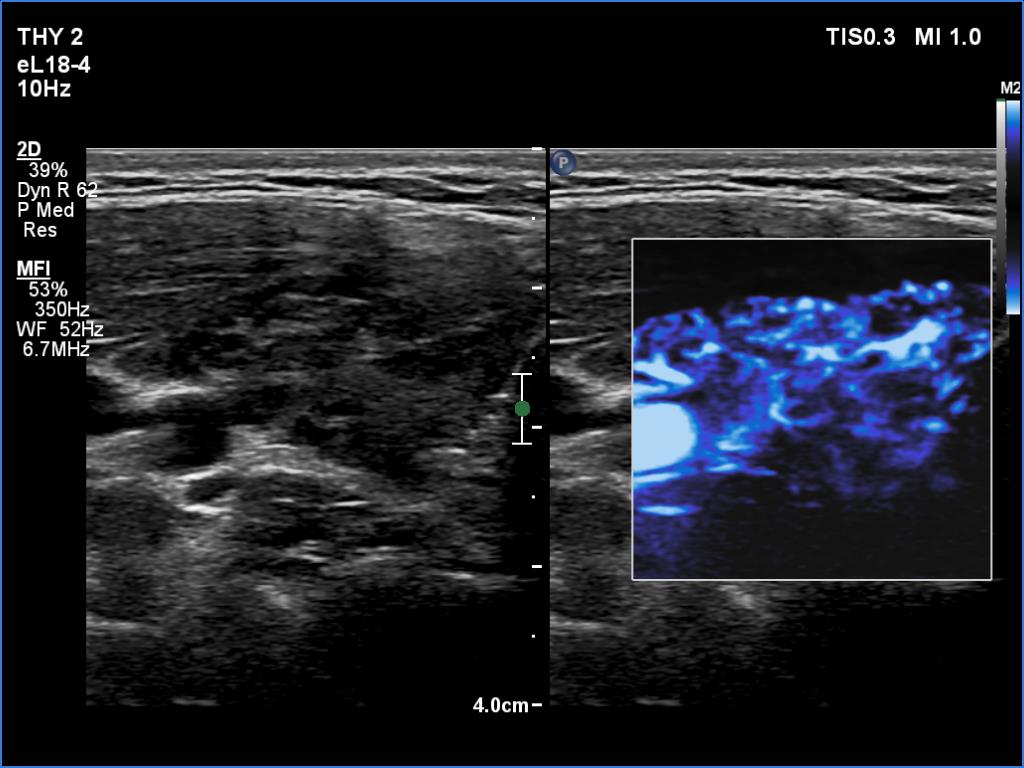

Right lobe, longitudinal scan

Right lobe, transverse view, microflow imaging. This modality disclosed vessels in regular distribution.